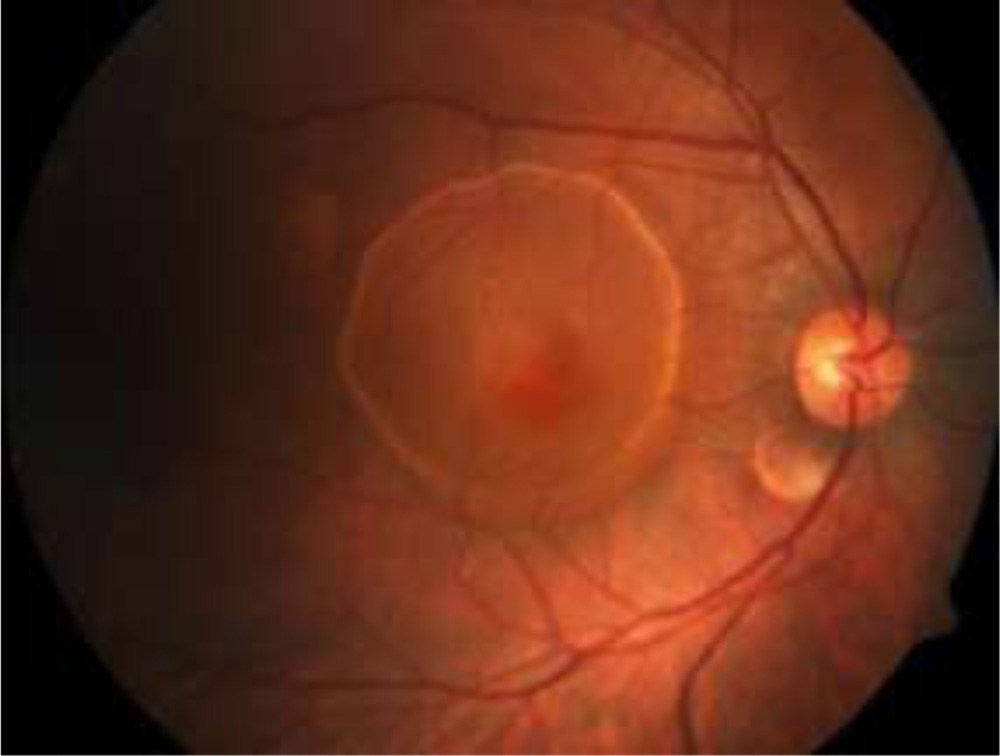

Figure 1 –Extra large PED

Figure 1 –Extra large PED